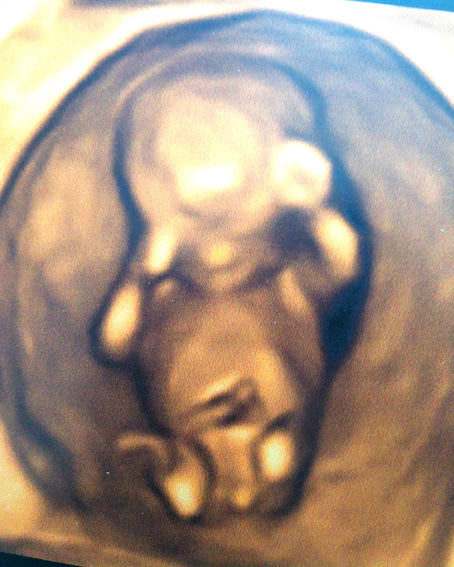

Hello, I would love some guess on the sex pls! Definitely can spot a clear 'nub' in the 3d shot, no idea about the 2d. Do all babies have this.. or is this clearly a boy in the making???! Happy with either!!

Too hard to tell from 3D shot you need to look at the angle of the nub when baby is lying flat on back. Fom your 2D shotI am guessing GIRL.